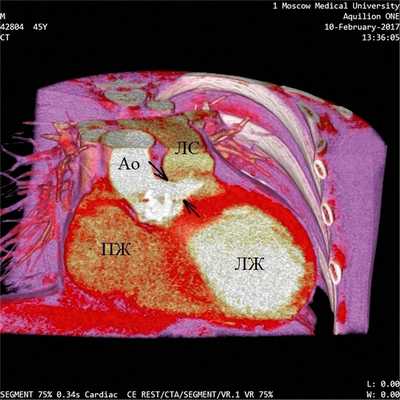

Предоперационное эхокардиографическое исследование выявило аневризму правого коронарного синуса с прорывом и формированием аорто-правожелудочковой фистулы, комбинированный аортальный порок с выраженным кальцинозом, тяжелым стенозом и недостаточностью, гипертрофию и дилатацию левого желудочка (конечный диастолический объем — 300 мл), снижение глобальной сократимости левого желудочка (фракция изгнания — 37%) на фоне диффузного снижения локальной, тяжелую трикуспидальную недостаточность, тяжелую легочную гипертензию. Порок сердца подтвержден данными МСКТ (см. рисунок). При КТ-коронароангиографии поражения коронарного русла не обнаружено. От проведения дооперационной терапии левосименданом мы вынуждены были отказаться по причине наличия у пациента частой желудочковой экстрасистолии и пробежек желудочковой тахикардии по данным мониторирования ЭКГ по Холтеру.

Аорто-правожелудочковая фистула (мультиспиральная компьютерная томография). ЛЖ — левый желудочек, Ао — восходящая аорта, ПЖ — правый желудочек, ЛС — легочный ствол. Стрелками обозначен диаметр аорто-правожелудочковой фистулы. Слева от фистулы визуализируется кальцинированный аортальный клапан.